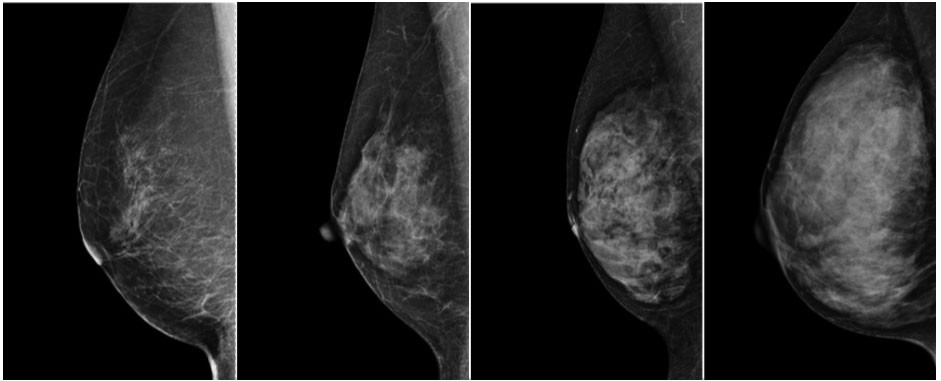

高濃度乳房(デンスブレスト)とは、乳腺組織が多く、乳房全体が白く映るタイプの乳房を指します。マンモグラフィでは、乳腺も乳がんも白く映るため、乳腺が多いとがんの影が隠れて見つかりにくくなる特徴があります。

日本人女性は欧米と比べて乳腺の割合が多く、高濃度乳房に該当する方が比較的多いといわれています。特に40代以下の女性では、高濃度乳房であるケースが目立ちます。